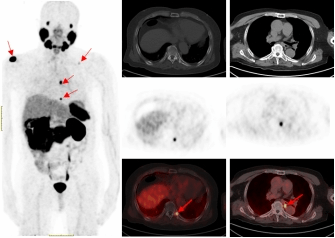

一名75的岁男性患者自2019年确诊前列腺癌后,先后接受过两次内分泌治疗及前列腺癌根治术的综合治疗。在术后两年的复查中发现血PSA持续升高,CT检查和全身骨显像检查均未发现明显异常,医生建议随诊,患者来到球友会官网附属医院要求进一步检查。经核医学科68Ga-PSMA PET/CT检查后结果显示,双侧肩胛骨、左侧第9后肋、第2腰椎及纵隔淋巴结均已存在癌症转移。